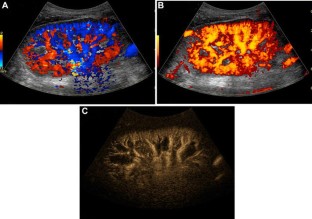

Fig. 4